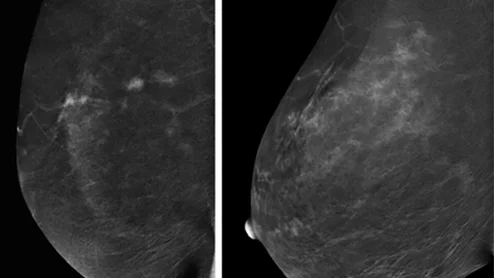

Interval breast cancer rates on the rise.

Thanks to AI, clinicians can use mammograms to do a lot more than identify signs of breast cancer. Researchers explored data from nearly 50,000 patients, presenting their findings in Heart.